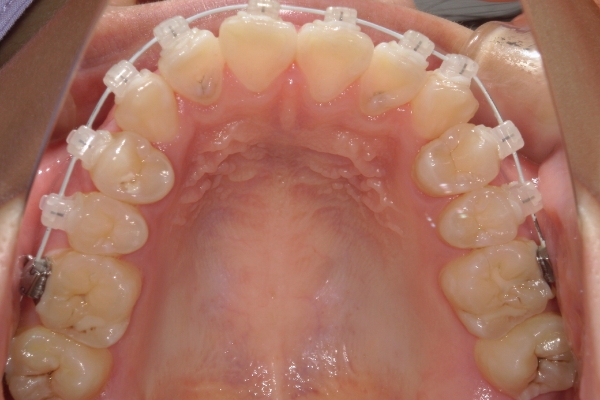

BEFORE

治療前

PROCESS

3か月

AFTER

治療後

骨格的に下あごが前下方に長いことが原因で、受け口、開咬(前歯が当たらない)の症状がでていました。また下あごが右にずれており、その影響で上下の歯列正中(真ん中)の大きなずれも生じていました。顎変形症手術も選択肢の一つでしたが、患者さまの希望もあり、下顎左側小臼歯の抜歯をして通常の歯列矯正で治療をしました。

前歯、奥歯の噛み合わせが大きく改善され、上下の歯真ん中が一致しました。食べ物が噛みやすくなったこともですが、歯列の見た目が整った点にも患者さまは満足されていました。